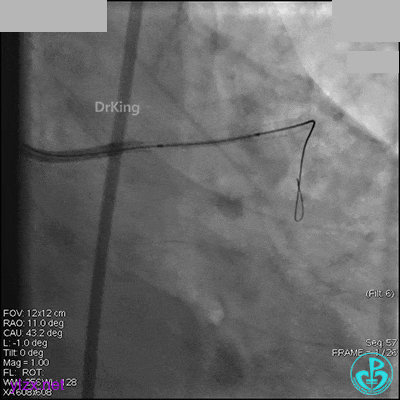

AL 1.0指引导管到位,简单短时尝试导丝不能顺利通过前降支或回旋支病变。改变策略处理右冠脉病变,计划植入2枚支架。AL指引导管到位,Sion blue导丝到达右冠脉远端。导丝通过后1.5mm及2.5mm球囊14~16atm充分扩张中段病变。

右冠脉中段充分扩张后欲植入3.5×38mm支架时,支架难以通过中远段扭曲处,且指引导管、导丝弹出飞扬。反复尝试导丝重新到达右冠脉远端时通过不顺利,局部造影剂滞留,远端血流接近3级。